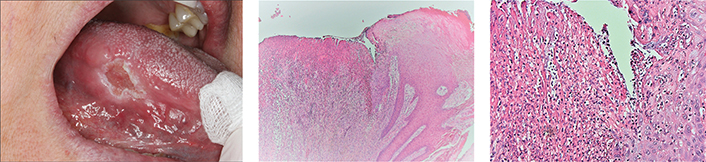

In June 2015, the patient reported increased pain from the enlarged ulcer without improvement of symptoms. A new excision was performed (Figure 2a), where HPE did not show any signs of dysplasia, but revealed an ulceration with fibrinous crusta, inflammation, and extensive infiltrates of neutrophil granulocytes (Figure 2b and c). At a revisit in September 2015, there was an ulcer with fungal infection. Fluconazole was administered, and the patient was called in for re-examination in December 2015. At that point, the lesion had developed an exophytic appearance on the lateral side of the tongue (Figure 3). In February 2016, treatment with radiofrequency ablation of the tongue was carried out (Figure 4). HPE displayed moderately to severely inflamed mucosa, with fibrosis and an ulcer consisting of eosinophil-rich infiltrates with candida infection. There were still no signs of malignancy or dysplasia. Antimycotics were administered.

Fig 2

Figure 2. (a) In June 2015 an increase in size of the ulcer was seen and an excision was performed. (b) & (c) Micrographs showing ulceration with fibrinous crusta and infiltrate of neutrophil granulocytes. Hematoxyline and eosin staining at × 40 (2b) and × 400 (2c).